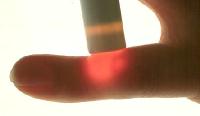

Case 2: Firm mass arising just distal to the PIP joint, fixed to deep structures.

Xray shows a contour change of the middle phalanx deep to the tumor.

Transillumination is indeterminate, slightly darker than surrounding tissues.